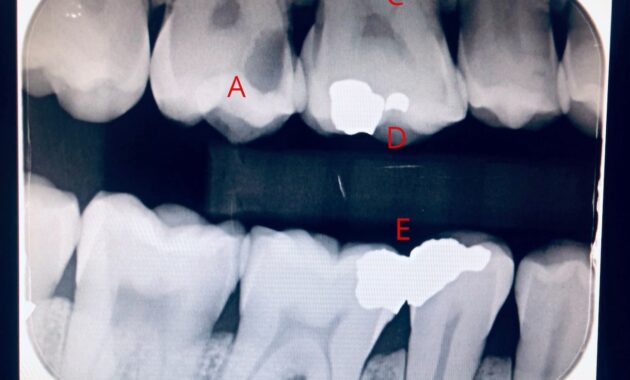

X-rays operate on a simple yet ingenious principle: different substances absorb radiation at varying rates. Teeth, being dense and calcified structures, appear prominently on X-ray films, often as white or light gray areas. However, the presence of cavities introduces a distinct contrast. When a cavity forms, it represents a loss of mineral content in the tooth, resulting in an area that absorbs less radiation than the surrounding healthy tooth structure. Consequently, these areas manifest as dark spots or shadows on the X-ray.

The appearance of a cavity on a dental X-ray can vary depending on its progression. Early-stage cavities may initially show up as subtle, smudgy areas of radiolucency—dark patches that may not draw immediate attention. As the decay advances, the shadows become more pronounced and larger, indicating a deeper invasion into the tooth’s anatomy. Dentists often categorize cavities based on their depth, where Class I lesions are confined to the pits and fissures of teeth, whereas Class II involves the proximal surfaces, and more severe cases penetrate the pulpal region.

Moreover, it’s not just the shape or darkness of a cavity that provides diagnostic clues. The location of the cavity is equally telling. Cavities often form in specific areas where plaque tends to accumulate. These include the fissures of the molars—those deep grooves designed for grinding food—and the interproximal areas between teeth, where toothbrush bristles may fail to reach. On an X-ray, a dentist can discern these common locations, which inform strategies for preventive treatment and patient education.